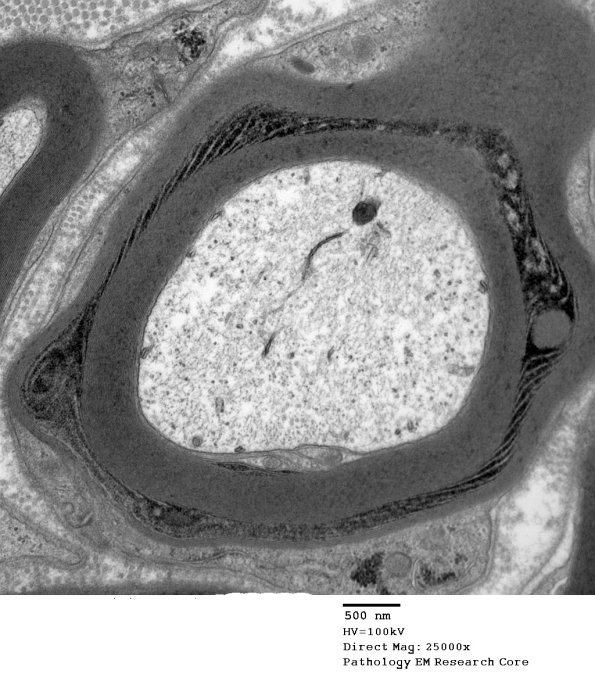

Multiple examples of circumferential SCL at several magnifications from the same case rich in them. (Electron micrographs)